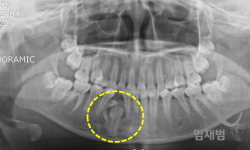

• 매복치